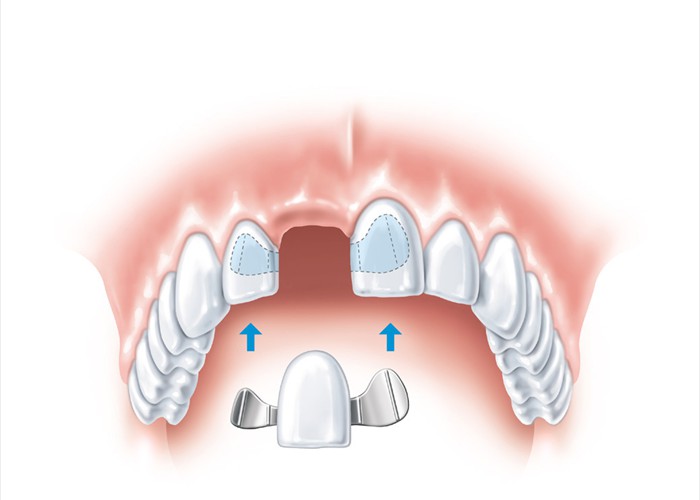

Weniger invasiv wäre eine Klebebrücke (Maryland Brücke)

Weniger invasiv wäre eine Klebebrücke (Maryland Brücke)

Die beste und zahnschonendste Lösung ist ein Implantat.

Die beste und zahnschonendste Lösung ist ein Implantat.